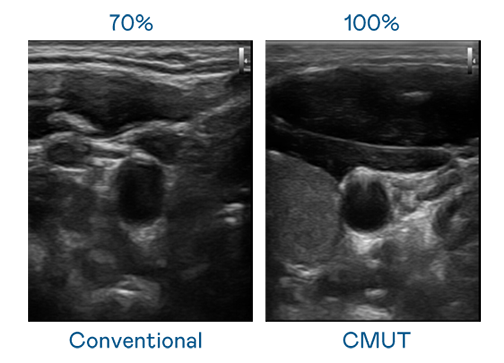

CMUT 技术是一种用电容式微机电元件来产生超音波讯号的技术。与传统 PZT 压电式技术相比,CMUT 频宽增加 30%,更宽频的超音波讯号让影像解析度大幅提升,是实现高影像品质医疗超音波扫描、促进精准医疗发展的关键技术。

超音波影像的解析度高低,首先取决于探头能发出的讯号频宽。wepoker微扑克 CMUT 可提供高清晰的超音波讯号,提供高频宽、高灵敏度、影像纹理细节更高的超音波影像,协助医护人员缩短影像判读时间及利用精准的医疗影像进行诊断。